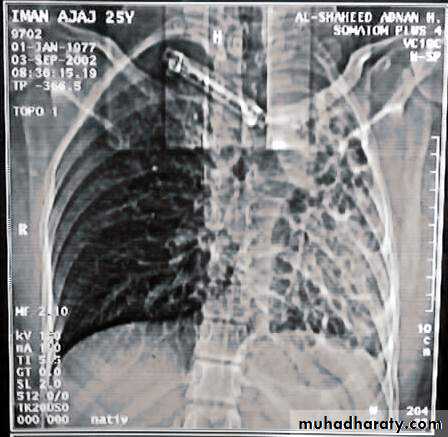

• Radiological Findings

• 1-Smooth homogenous opacity (Intact H.C).• 2-Partial rupture (per vesicular pneumocyst).

• 3-Complete rupture (Water –lilly sign) .

• 4-Formation of lung abscess(Air –fluid level) .

• 5-Completely coughed out cyst(empty cavity )

• 6-Rupture into the pleura (hydropneumothorax)